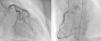

Angiography revealed absence of obstructive coronary disease or acute plaque rupture (Figure 1). Ventriculography showed apical and midventricular dysfunction with hyperkinesis of the basal myocardial segments and severely depressed ejection fraction (Figure 2). A second detailed transthoracic echocardiographic examination confirmed apical akinesis, basal hyperkinesis and severe systolic left ventricular (LV) dysfunction; apical ballooning syndrome was confirmed.